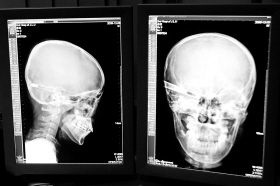

“還是先做個(gè)X光透視,看一下箭桿到底有多深!毖劭漆t(yī)生緊急趕到CT室查看,和放射科的幾位醫(yī)生共同研究后,決定先讓小沖做X光透視。

“如果再用點(diǎn)力,就從后腦穿出來了!”由于小沖無法移動(dòng),醫(yī)生拿來移動(dòng)插座,將透視的光板放在小沖的移動(dòng)病床上,透視后讓在場的醫(yī)生都吃了一驚:箭桿直接穿過了大腦和小腦,箭尖兒直抵后顱骨,足足有10余厘米。